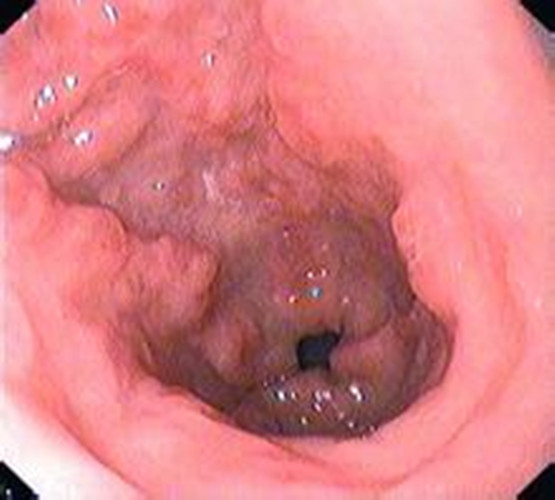

慢性胃炎